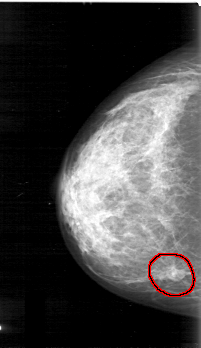

D_4031_1.LEFT_MLO

LEFT_MLO LINES 5221 PIXELS_PER_LINE 3136 BITS_PER_PIXEL 12 RESOLUTION 43.5 NON_OVERLAY

FILE: D_4031_1.RIGHT_MLO.OVERLAY

TOTAL_ABNORMALITIES 1

ABNORMALITY 1

LESION_TYPE MASS SHAPE OVAL MARGINS OBSCURED

ASSESSMENT 0

SUBTLETY 5

PATHOLOGY BENIGN

TOTAL_OUTLINES 1

BOUNDARY